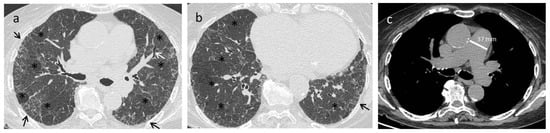

| Early stage | NSIP pattern:

|

| Late fibrotic stage | Fibrotic NSIP/UIP pattern: